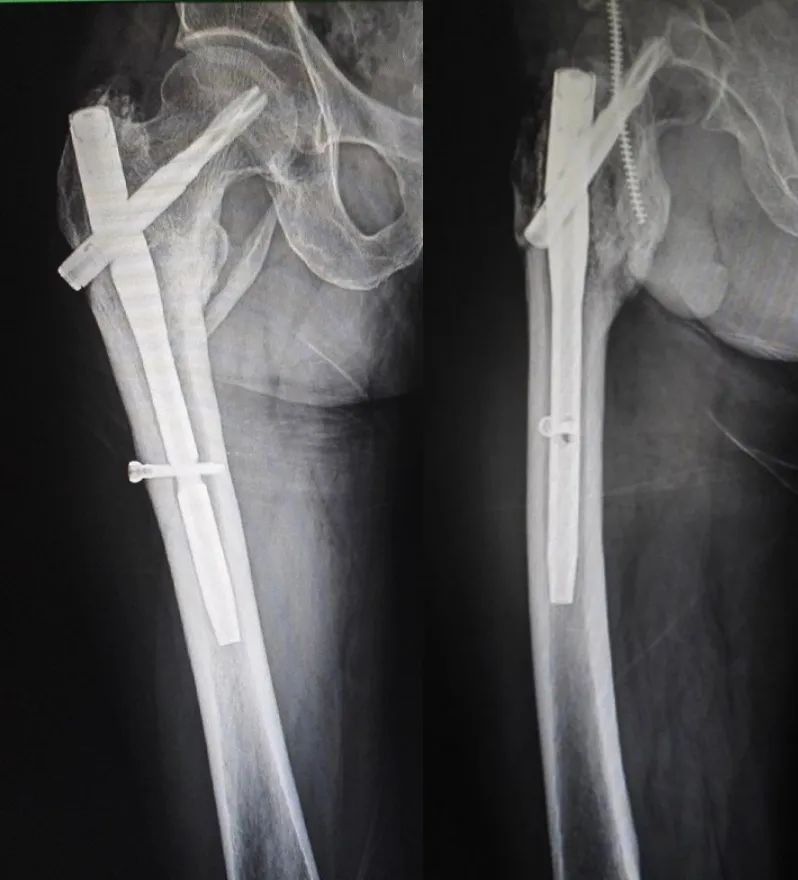

治疗经过:入院后行持续右下肢骨牵引,牵引五天后行 PFNA 内固定术。

手术后 X 线片

术后 21 个月 X 线片:

患者术后一年半有余,要求去除内固定物来院,未诉不适,大意了,术前阅片不仔细,术中拆除锁钉、螺旋刀片和尾帽,拔主钉后傻眼了 —— 只拔出了上三分之一 ,回头再看片子才发现主钉刚好在螺旋刀片处断裂了。